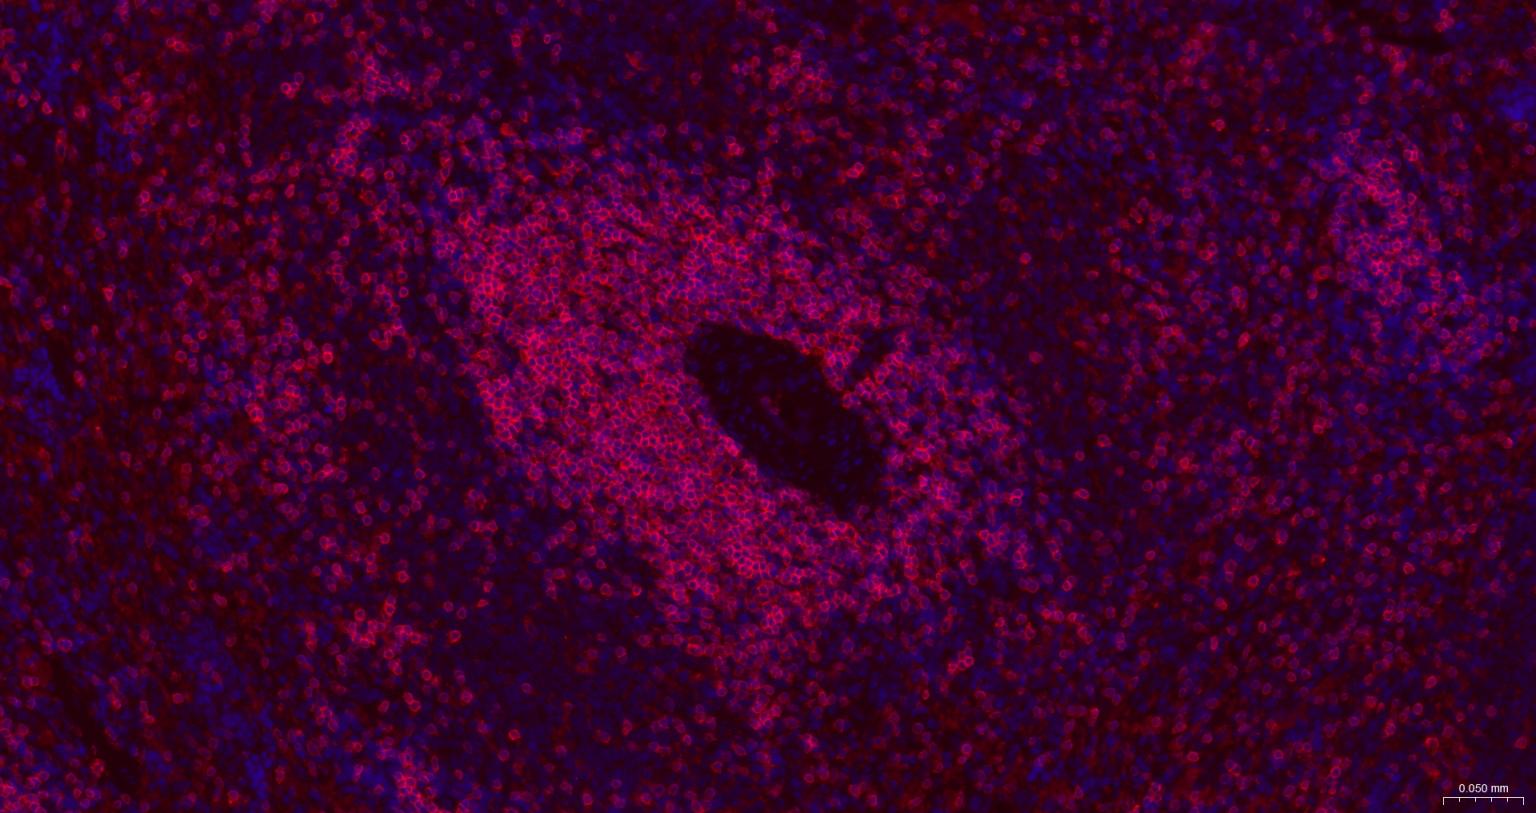

IHC-FHuman, Mouse, Rat1:500-2000

IFHuman, Mouse, Rat1:500-2000